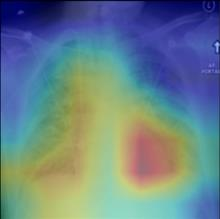

Thoracic disease detection from chest radiographs using deep learning methods has been an active area of research in the last decade. Most previous methods attempt to focus on the diseased organs of the image by identifying spatial regions responsible for significant contributions to the model's prediction. In contrast, expert radiologists first locate the prominent anatomical structures before determining if those regions are anomalous. Therefore, integrating anatomical knowledge within deep learning models could bring substantial improvement in automatic disease classification. This work proposes an anatomy-aware attention-based architecture named Anatomy X-Net, that prioritizes the spatial features guided by the pre-identified anatomy regions. We leverage a semi-supervised learning method using the JSRT dataset containing organ-level annotation to obtain the anatomical segmentation masks (for lungs and heart) for the NIH and CheXpert datasets. The proposed Anatomy X-Net uses the pre-trained DenseNet-121 as the backbone network with two corresponding structured modules, the Anatomy Aware Attention (AAA) and Probabilistic Weighted Average Pooling (PWAP), in a cohesive framework for anatomical attention learning. Our proposed method sets new state-of-the-art performance on the official NIH test set with an AUC score of 0.8439, proving the efficacy of utilizing the anatomy segmentation knowledge to improve the thoracic disease classification. Furthermore, the Anatomy X-Net yields an averaged AUC of 0.9020 on the Stanford CheXpert dataset, improving on existing methods that demonstrate the generalizability of the proposed framework.